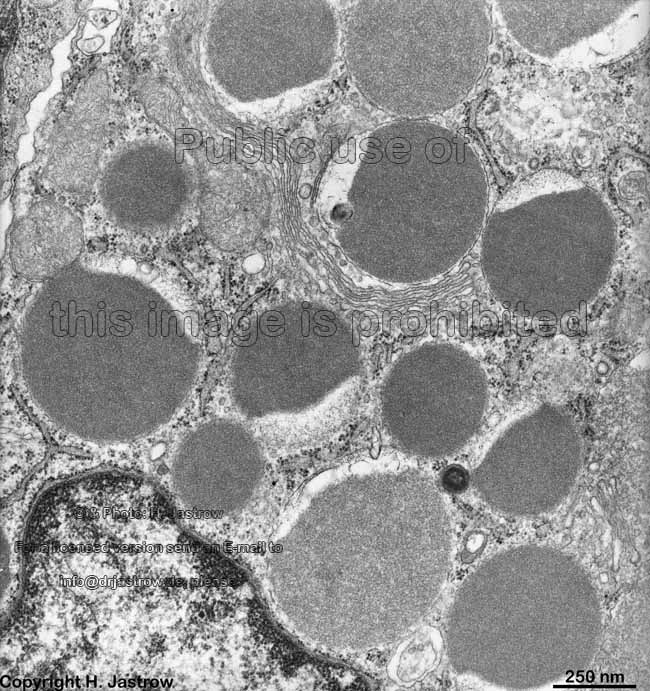

Miniaturbildübersicht Krummdarm (Ileum):

Lysozym-haltige

Vesikel (Ratte)

idem Detail (Ratte)